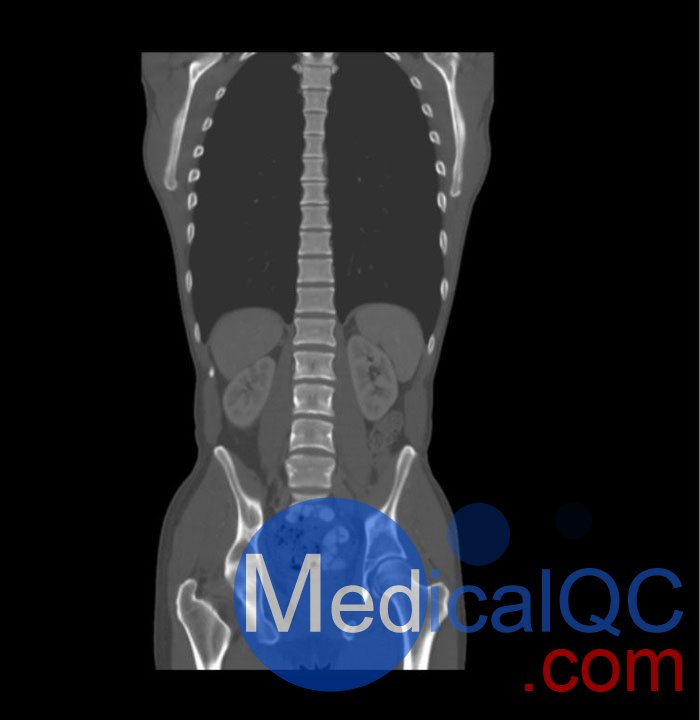

WEK57-01門靜脈期軀干模體,WEK57-01軀干模型模擬了門靜脈期的造影劑增強(qiáng)胸部、腹部和骨盆。它覆蓋了會陰的第二胸椎。

右側(cè)有髂淋巴結(jié)腫塊。

該模型可用于 CT(包括 CBCT)以評估和優(yōu)化成像性能和后處理應(yīng)用,包括支持 AI 的應(yīng)用。它也適用于培訓(xùn)目的。

該模型提供了對軟組織和骨組織的詳細(xì)而逼真的模擬。包括肺在內(nèi)的空隙充滿了大約 -160HU的纖維素聚合物復(fù)合材料。

真實模擬脈管系統(tǒng)、骨骼和軟組織,包括肺、心臟、肝臟、膽囊、胰腺、脾臟、腎上腺、腎臟、胃、小腸、結(jié)腸、膀胱和前列腺。

右側(cè)髂外淋巴結(jié)腫塊。

大?。?約 267 x 185 x 466 mm

重量: 約 11040 g

基材: 纖維素-聚合物復(fù)合材料

最佳管電壓: 120 kVp – 可根據(jù)要求進(jìn)行調(diào)整

WEK57-01門靜脈期軀干模體,WEK57-01軀干模型成像效果圖: